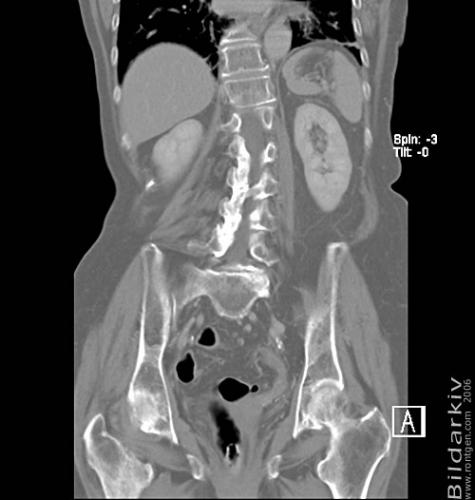

CT colon 36

Datortomografi av tjocktarmen (colon) med infunderad luft i tarmen samt med kontrast i blodbanan. Koronar bildserie.

CT multislice 16